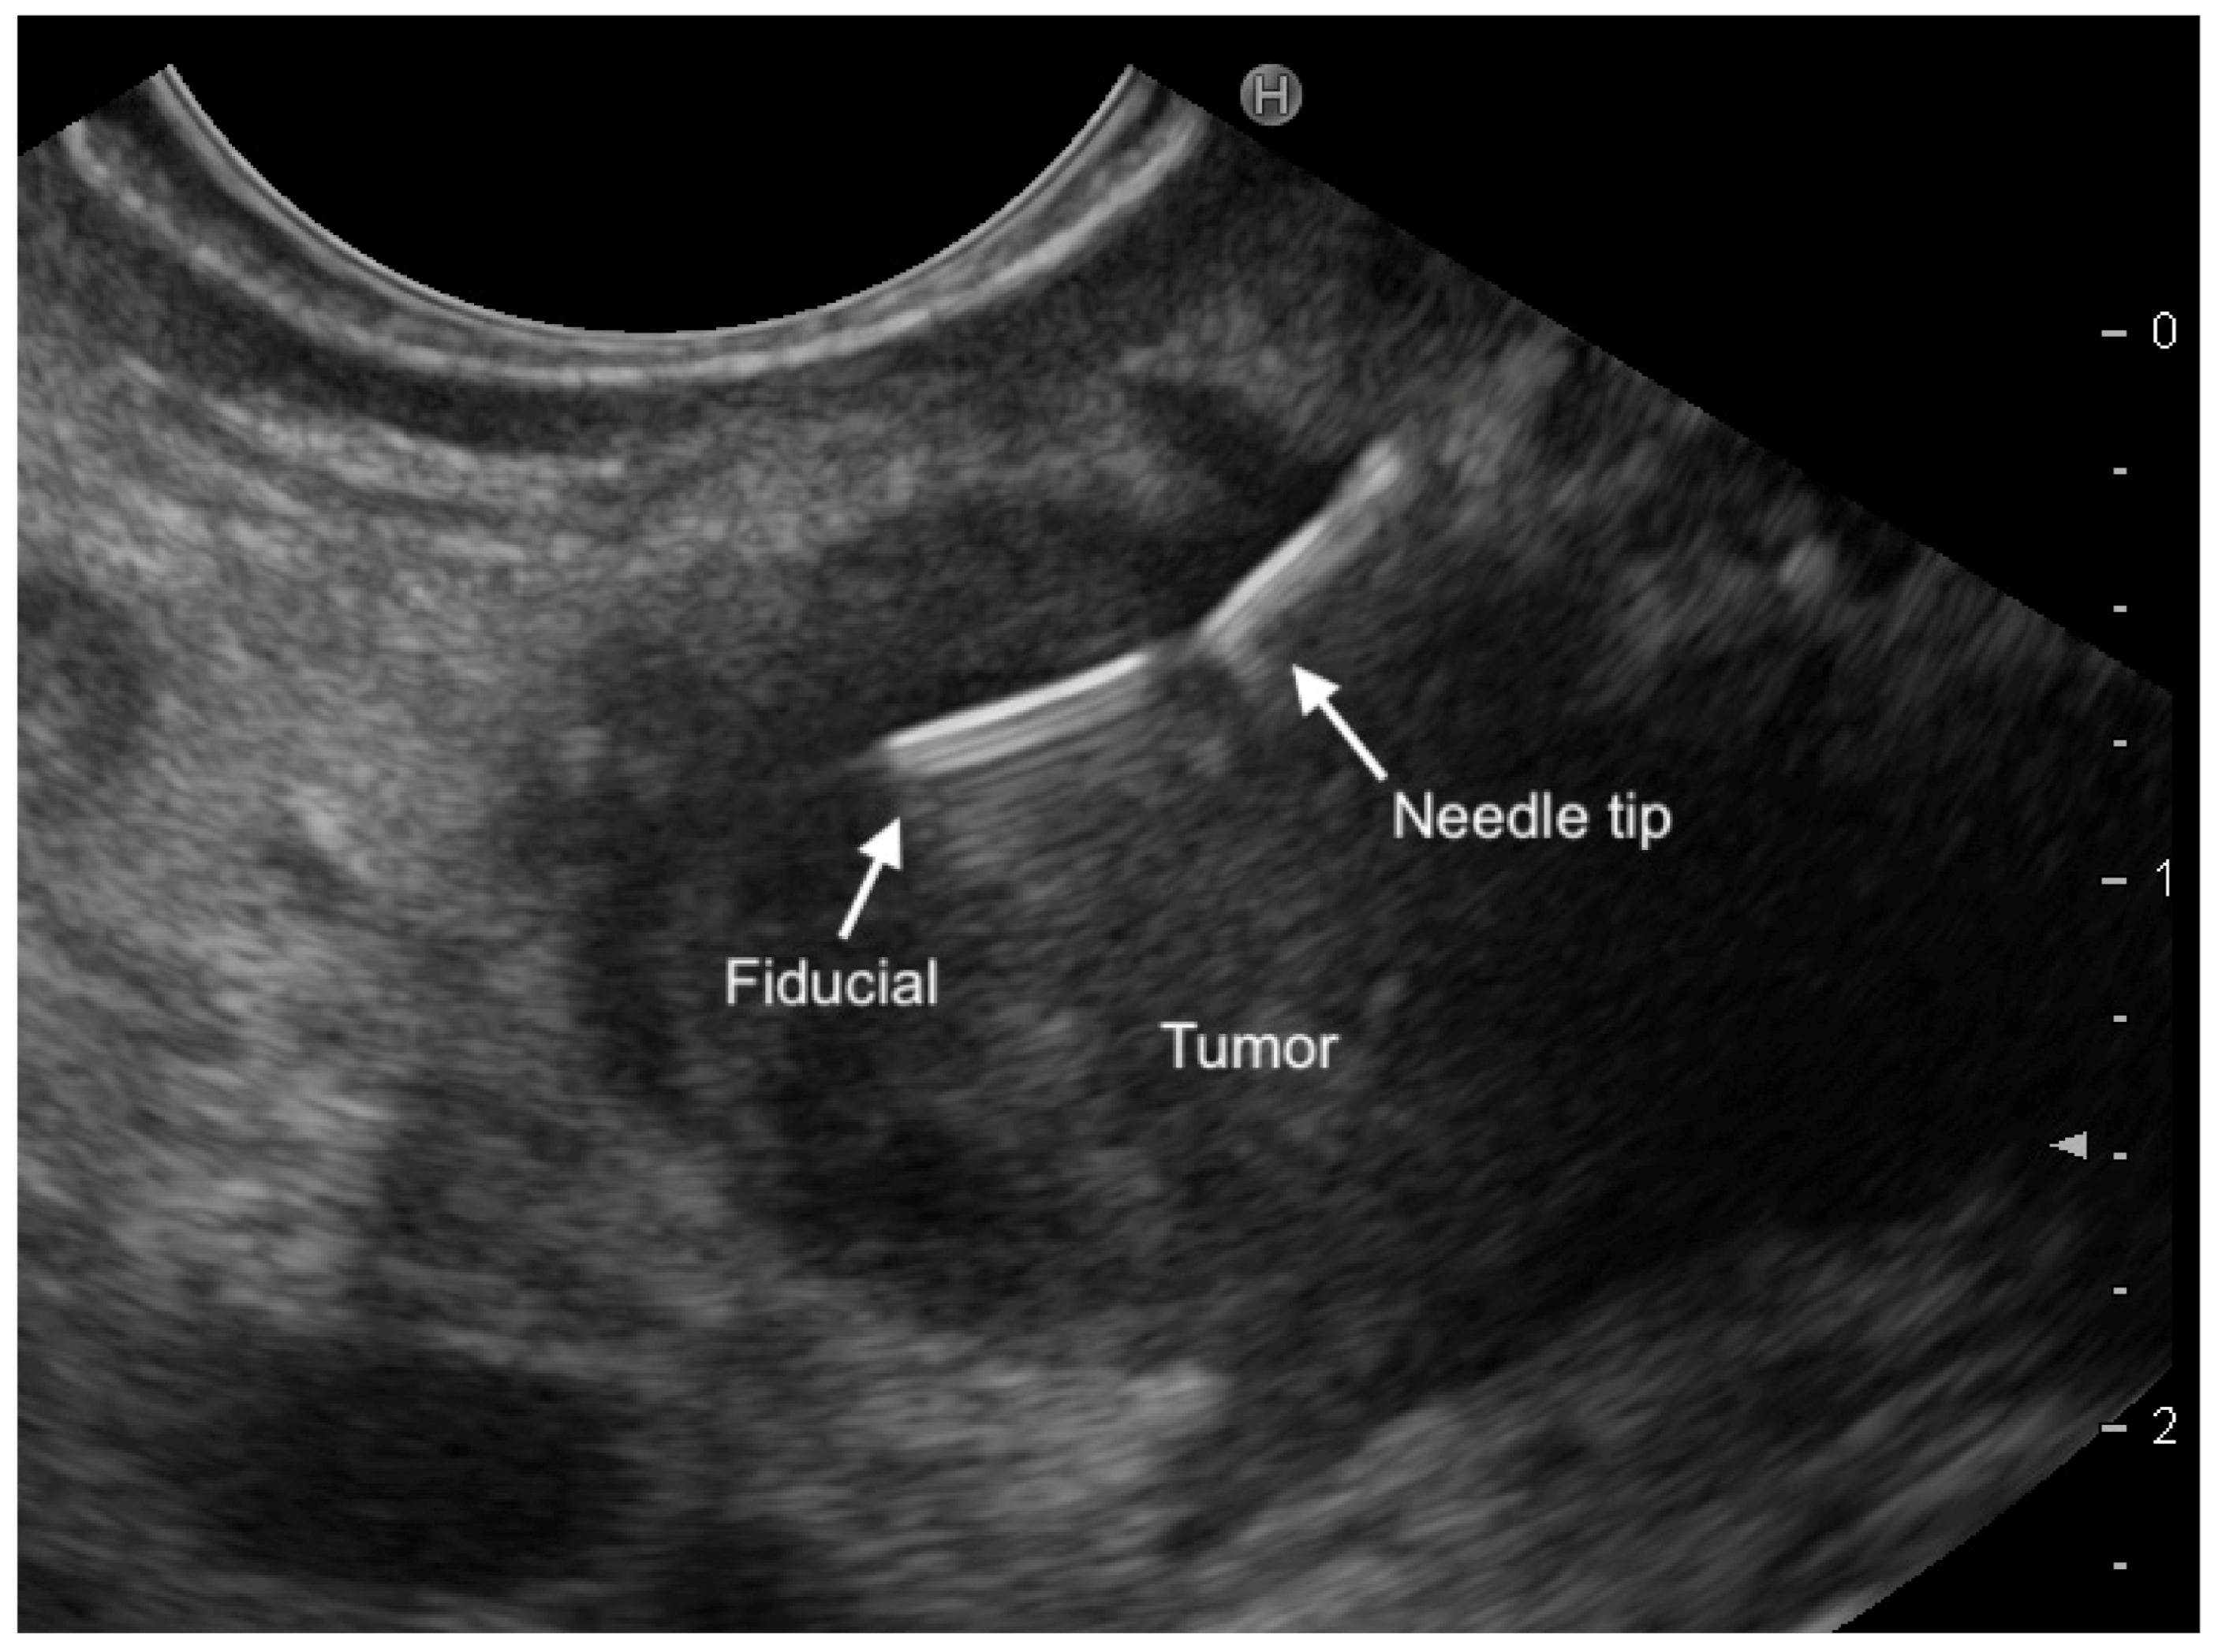

3.1. EUS-Fine-Needle-Tattooing (EUS-FNT) and EUS-Guided Fiducial Implantation (EUS-FI)

- Law, J.K.; Singh, V.K.; Khashab, M.A.; Hruban, R.H.; Canto, M.I.; Shin, E.J.; Saxena, P.; Weiss, M.J.; Pawlik, T.M.; Wolfgang, C.L.; et al. Endoscopic ultrasound (EUS)-guided fiducial placement allows localization of small neuroendocrine tumors during parenchymal-sparing pancreatic surgery. Surg. Endosc. 2013, 27, 3921–3926. [Google Scholar] [CrossRef]

- Leelasinjaroen, P.; Manatsathit, W.; Berri, R.; Barawi, M.; Gress, F.G. Role of preoperative endoscopic ultrasound-guided fine-needle tattoing of pancreatic head insulinoma. World J. Gastrointest Endosc. 2014, 6, 506–509. [Google Scholar] [CrossRef]

- Gress, F.G.; Barawi, M.; Kim, D.; Grendell, J.H. Preoperative localization of neuroendocrine tumor of the pancreas with EUS-guided fine needle Tattoing. Gastrointest. Endosc. 2002, 55, 594–597. [Google Scholar] [CrossRef]

- Lennon, A.M.; Newman, N.; Makary, M.A.; Edil, B.H.; Shin, E.J.; Khashab, M.A.; Hruban, R.H.; Wolfgang, C.L.; Schulick, R.D.; Cando, S.G.M.I. EUS-guided tattoing before laparoscopic distal pancreatic resection. Gastrointest. Endosc. 2010, 72, 1089–1094. [Google Scholar] [CrossRef]